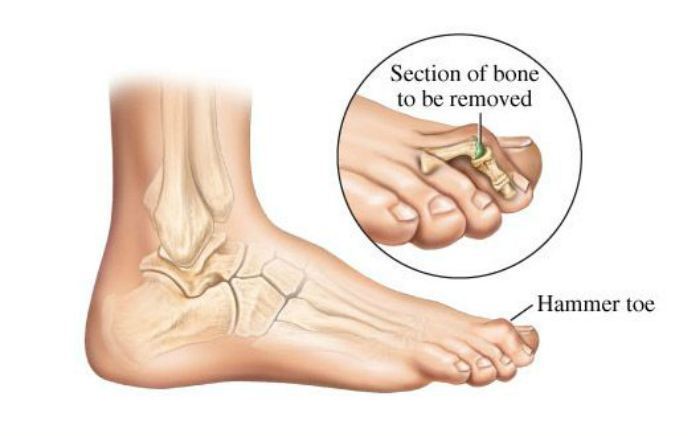

Common Foot & Ankle Disorders

Did you know the foot has 26 bones, 33 joints, 107 ligaments, 19 muscles, and numerous tendons? These parts all work together to allow the foot to move in a variety of ways while balancing your weight and propelling you forward or backward on even or uneven surfaces. It is no wonder that 75 percent of all Americans will experience foot problems at one point or another in their lifetimes.